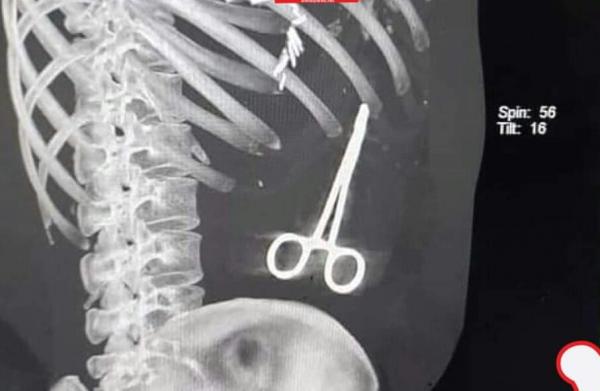

اكتشف أطباء في مستشفى مأرب وجود مقص في بطن مواطن، كان قد عاد من رحلة علاجية في العاصمة المصرية القاهرة.

وتابع: “بعد عودته إلى مأرب، وبعد عدة أيام، شعر أنس بآلام في منطقة البطن، وأُسعف، على إثرها، لتكشف الأشعة وجود أدوات حادة في بطنه، تم نسيانها من قِبل الجراح الذي أجرى العملية في وقت سابق”.